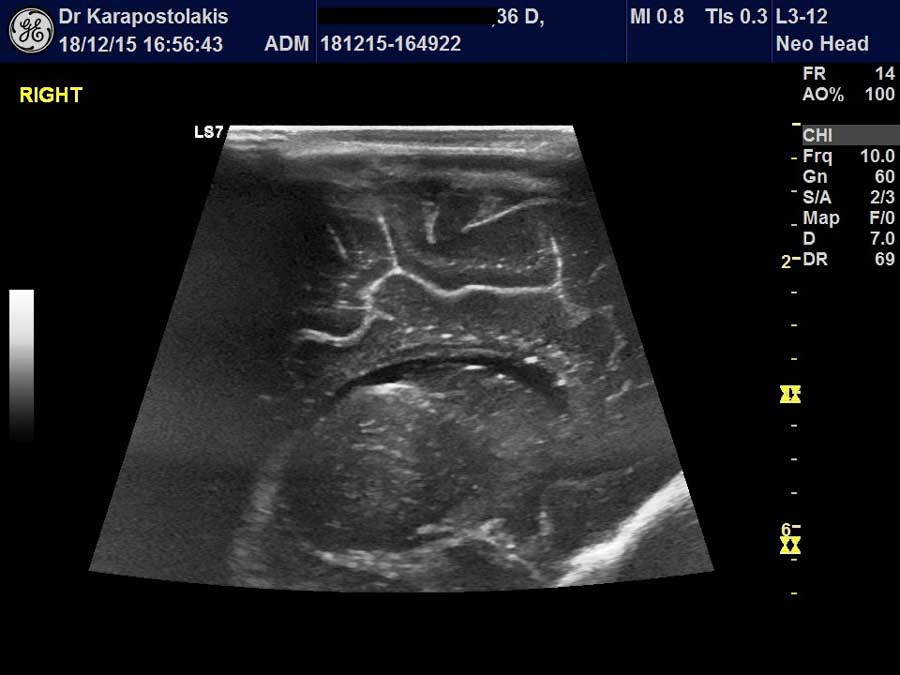

Πραγματοποιούνται στο Ιατρείο υπερηχογραφικές εξετάσεις σε παιδιά (από την νεογνική ηλικία μέχρι και την εφηβεία) και σε ενήλικες

Στα παιδιά διενεργούνται οι κάτωθι υπερηχογραφικές εξετάσεις

- Υπερηχογράφημα θυρεοειδούς αδένα και παραθυρεοειδών αδένων

- Υπερηχογράφημα τραχηλικών λεμφαδένων

- Υπερηχογράφημα αμυγδαλών

- Υπερηχογράφημα σιελογόνων αδένων (παρωτίδες, υπογνάθιοι και υπογλώσσιοι αδένες)

- Υπερηχογράφημα τραχήλου (συρίγγια, συγγενείς κύστεις, βραγχιακά υπολείμματα, κύστη θυρεογλωσσικού πόρου, έκτοπος θυμικός ιστός, βλάβες λεμφικού ιστού κ.α.)